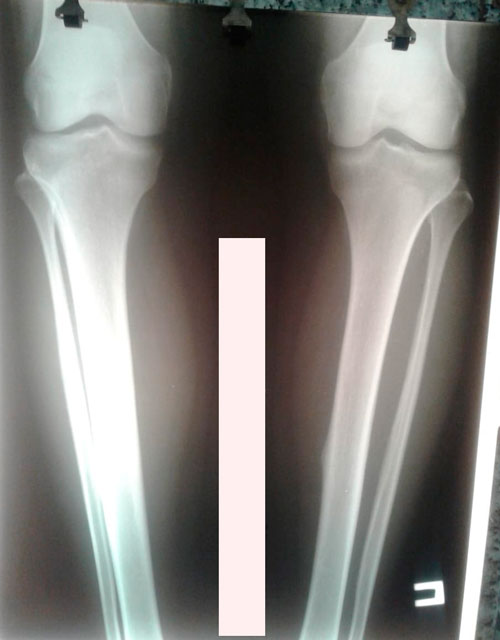

Исходник -34 года.Бишкек.

Дата операции - 26.02.2019г.

Дата снятия аппаратов - 05.06.2019г.

Срок сращения - 98 дней.